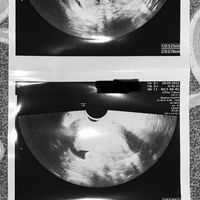

Eco ovulazione, sapreste aiutarmi a leggerla? Grazie 😔

Extra22, Il 1 Ottobre 2022 alle 07:36

Buongiorno, dopo il mio primo ciclo di clomid dal 3 al 7 giorno ho il primo monitoraggio all 11 giorno (mercoledì) in cui la ginecologa stranita mi dice di aver già ovulato. Io un po’ rimasta male...